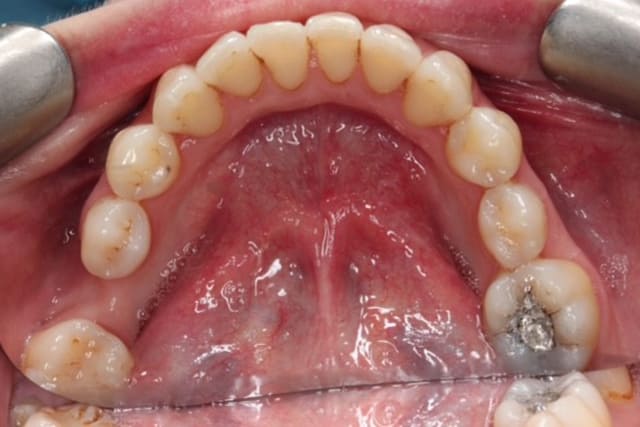

Dental Hygienist service after image – Bayswater Dental Clinic